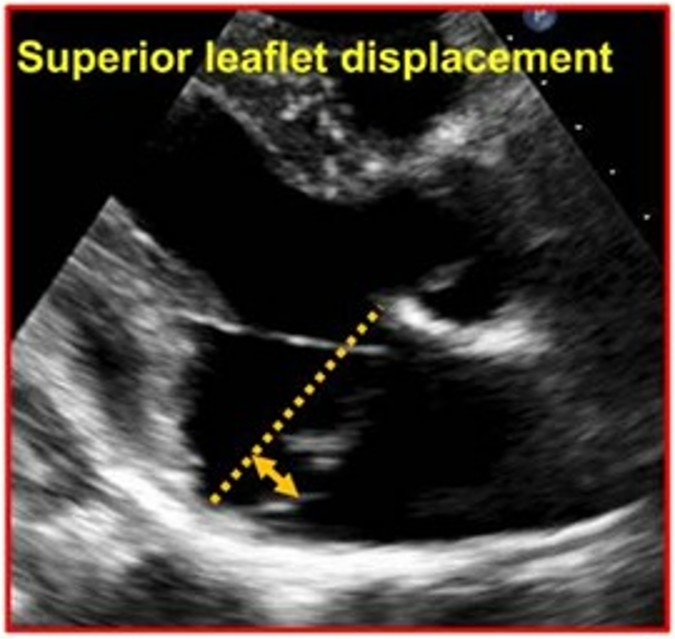

O prolapso foi definido como um deslocamento sistólico posterior (superior) do folheto valvar avaliado na janela paraesternal longitudinal eixo longo a partir do plano do anel mitral até o ponto mais superior do folheto prolapsado.

O curling consiste numa mobilidade exagerada do anel mitral posterior seguida de uma incursão miocárdica no segmento basal da parede ínfero lateral associado a um deslocamento superior do folheto posterior.